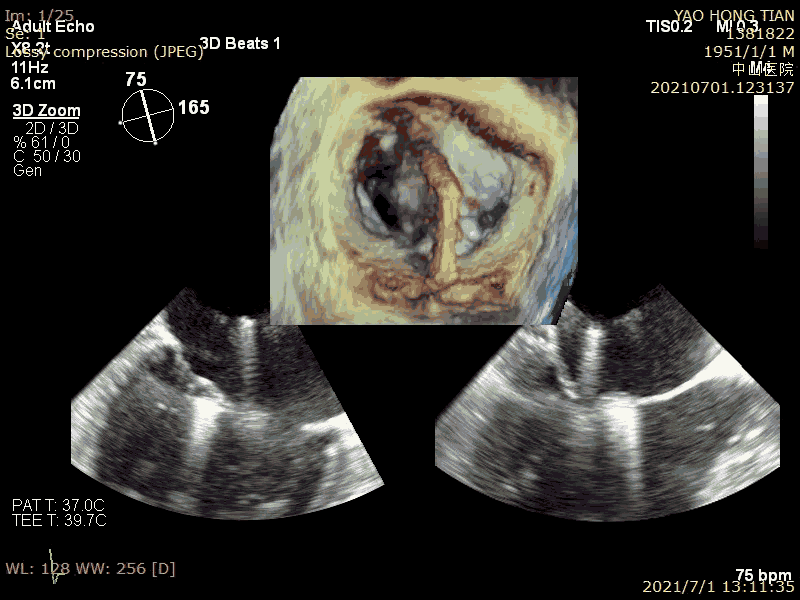

瓣膜捕获

半夹合评估效果

完全夹合评估效果